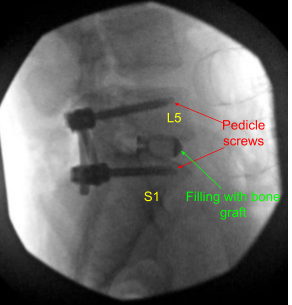

Once the dissection was done, the decision was made to put pedicle screws in both pedicles of S1 and L5. Drill was used to mark a pilot hole and a gearshift was used to guide the hole through the pedicle of S1 on either side under fluoroscopic guidance. Ball-tip sound was used to check the integrity of the canal.

Then 40 mm x 6 mm of pedicle screws (Depuy Synthes) were inserted on either pedicle of S1 and checked under fluoroscopy and found to be in satisfactory position. Similarly, a pilot hole was made with the use of drill on either side of the pedicle of L5 followed by a gearshift to find the path under fluoroscopy. A ball-tipped probe was again used and all the walls were found to be intact. Again, tapping was done and 6 mm x 45 mm pedicle screws were inserted in either pedicle.

A trial cage was inserted and checked under fluoroscopy and it was decided to put a 9 mm x 36 mm titanium cage. Allograft was used and mixed with morselized auto bone graft of the lamina and spinous process. The cage and disc interspace was filled with bone graft and the cage was inserted and checked under fluoroscopy, found to be in satisfactory position.

A thorough irrigation of the wound was done and decortication of the transverse process of both L5, sacral ala as well as parts on the right side was performed and bone graft was inserted over the Fibergraft. The 45-mm rods were used to connect the both pedicle screws on either side and the set screws were inserted and tightened and torqued.